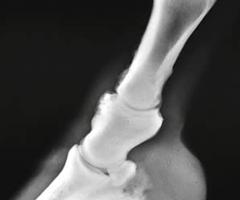

Kulno sąnario OCD (13 pav.) pasireiškia keliose skirtingose sąnario vietose: blauzdikaulio intermedialinėje keteroje, kulno distaliniame lateraliniame skridinyje, rečiau – blauzdikaulio plaktukėliuose ir kulno medialiniame skridinyje (Ross M.W., Dyson S.J., 2003, Bramlage L.R., 2006).

Diagnozuojant ligą, daromos 4 standartinės kulno sąnario rentgenogramos. Tai: dorsoplantarinė, lateromedialinė ir 2 įstrižos projekcijos. Iš jų dorsolateralinė ar dorsoplantarinė mediolateralinė įstrižos projekcijos suteikia daugiausiai informacijos (Ross M.W., Dyson S., 2003, Bramlage L.R., 2006).

13 pav. a) Medialinė įstriža kulnakaulio projekcija. b) Lateralinė kulnakaulio projekcija (cal.vet.upenn.edu ).